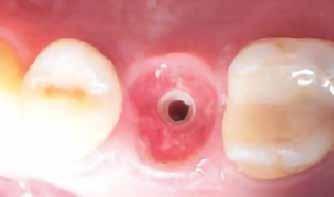

Azonnali ideiglenes fogpótlás

A műtétet követően önkötő akrilátból ideiglenes koronákat készítettünk, amelyeket cementtel rögzítettünk a cirkónium-dioxid ideiglenes fejeken (CR Zi Pillar®, 7. a–c ábrák ).

Utánkövetés

A végleges ragasztást követően röntgenfelvételt készítettünk, amelyet összevetettünk a közvetlenül a műtét után készült felvételekkel: a marginális csontszint változatlan volt. A pácienseket 14 hónapon keresztül rendszeresen visszahívtuk. Klinikai és röntgenvizsgálattal sem tapasztaltunk komplikációt (12. a–b ábrák)